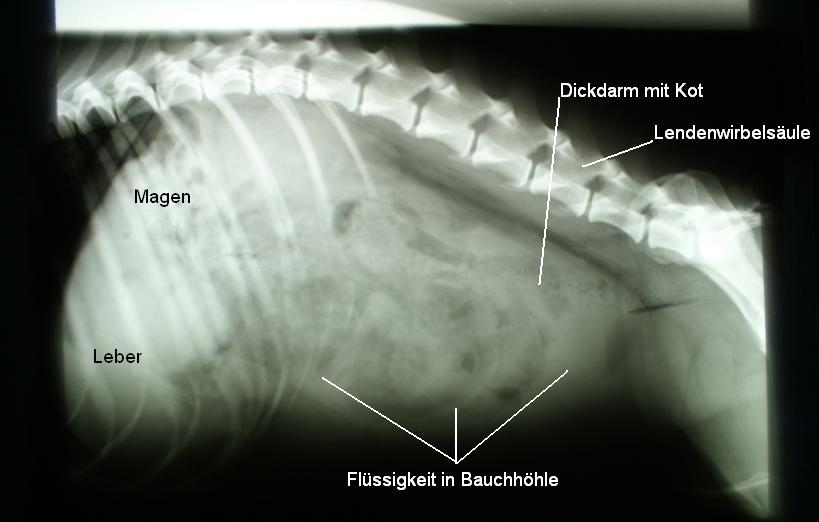

Auf einer Röntgenaufnahme des Bauches ist ersichtlich, dass die Organe schlecht voneinander abgrenzbar sind - in der Bauchhöhle befindet sich offenbar Flüssigkeit.